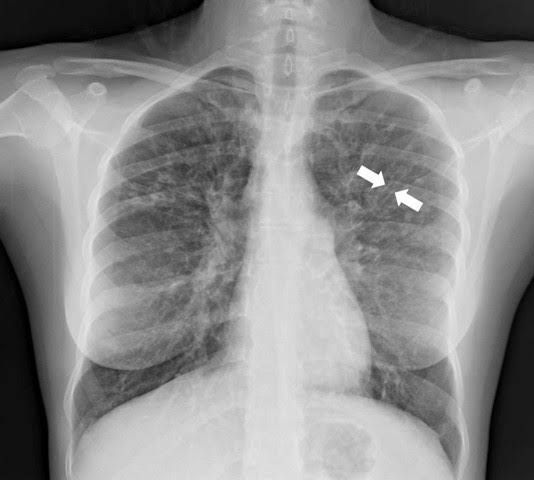

Bronchiectasis is a long-term condition where the airways of the lungs become widened, leading to a build-up of excess mucus that can make the lungs more vulnerable to infection. The most common symptoms of bronchiectasis include: a persistent cough that usually brings up phlegm (sputum)